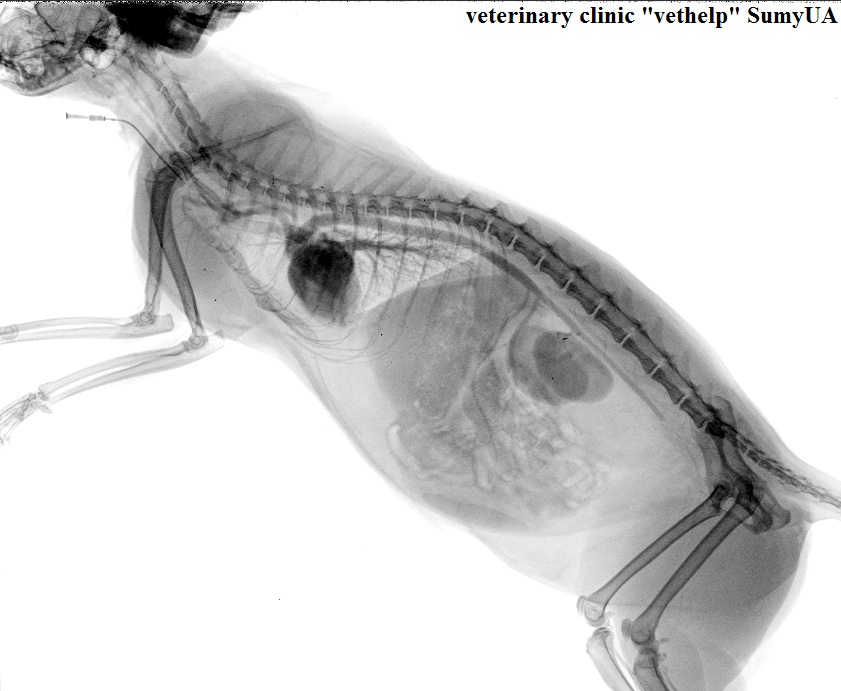

Ангиография (введение рентгенконтрастного вещества в сосуды, в результате чего на снимке (в течении нескольких сек.) становиться возможным видеть кровеносное русло): По результатам чего был поставлен диагноз - тромбоэмболия брюшной аорты у 5ти летнего кота с ГКМП (гипертрофическая кардиомиопатия диагноз поставлен по средством ЭХО-кардиграфии). Причина обращения: кот перестал ходить на задние лапы и сильно кричал от боли. На снимках видно начало введение контраста и его движение по сосудам, а также место где резко прерывается сосуд - эт и есть тромб :(

Снимок шотландской кошки с тромбозом и частичной проходимостью контраста в тазовые конечности.